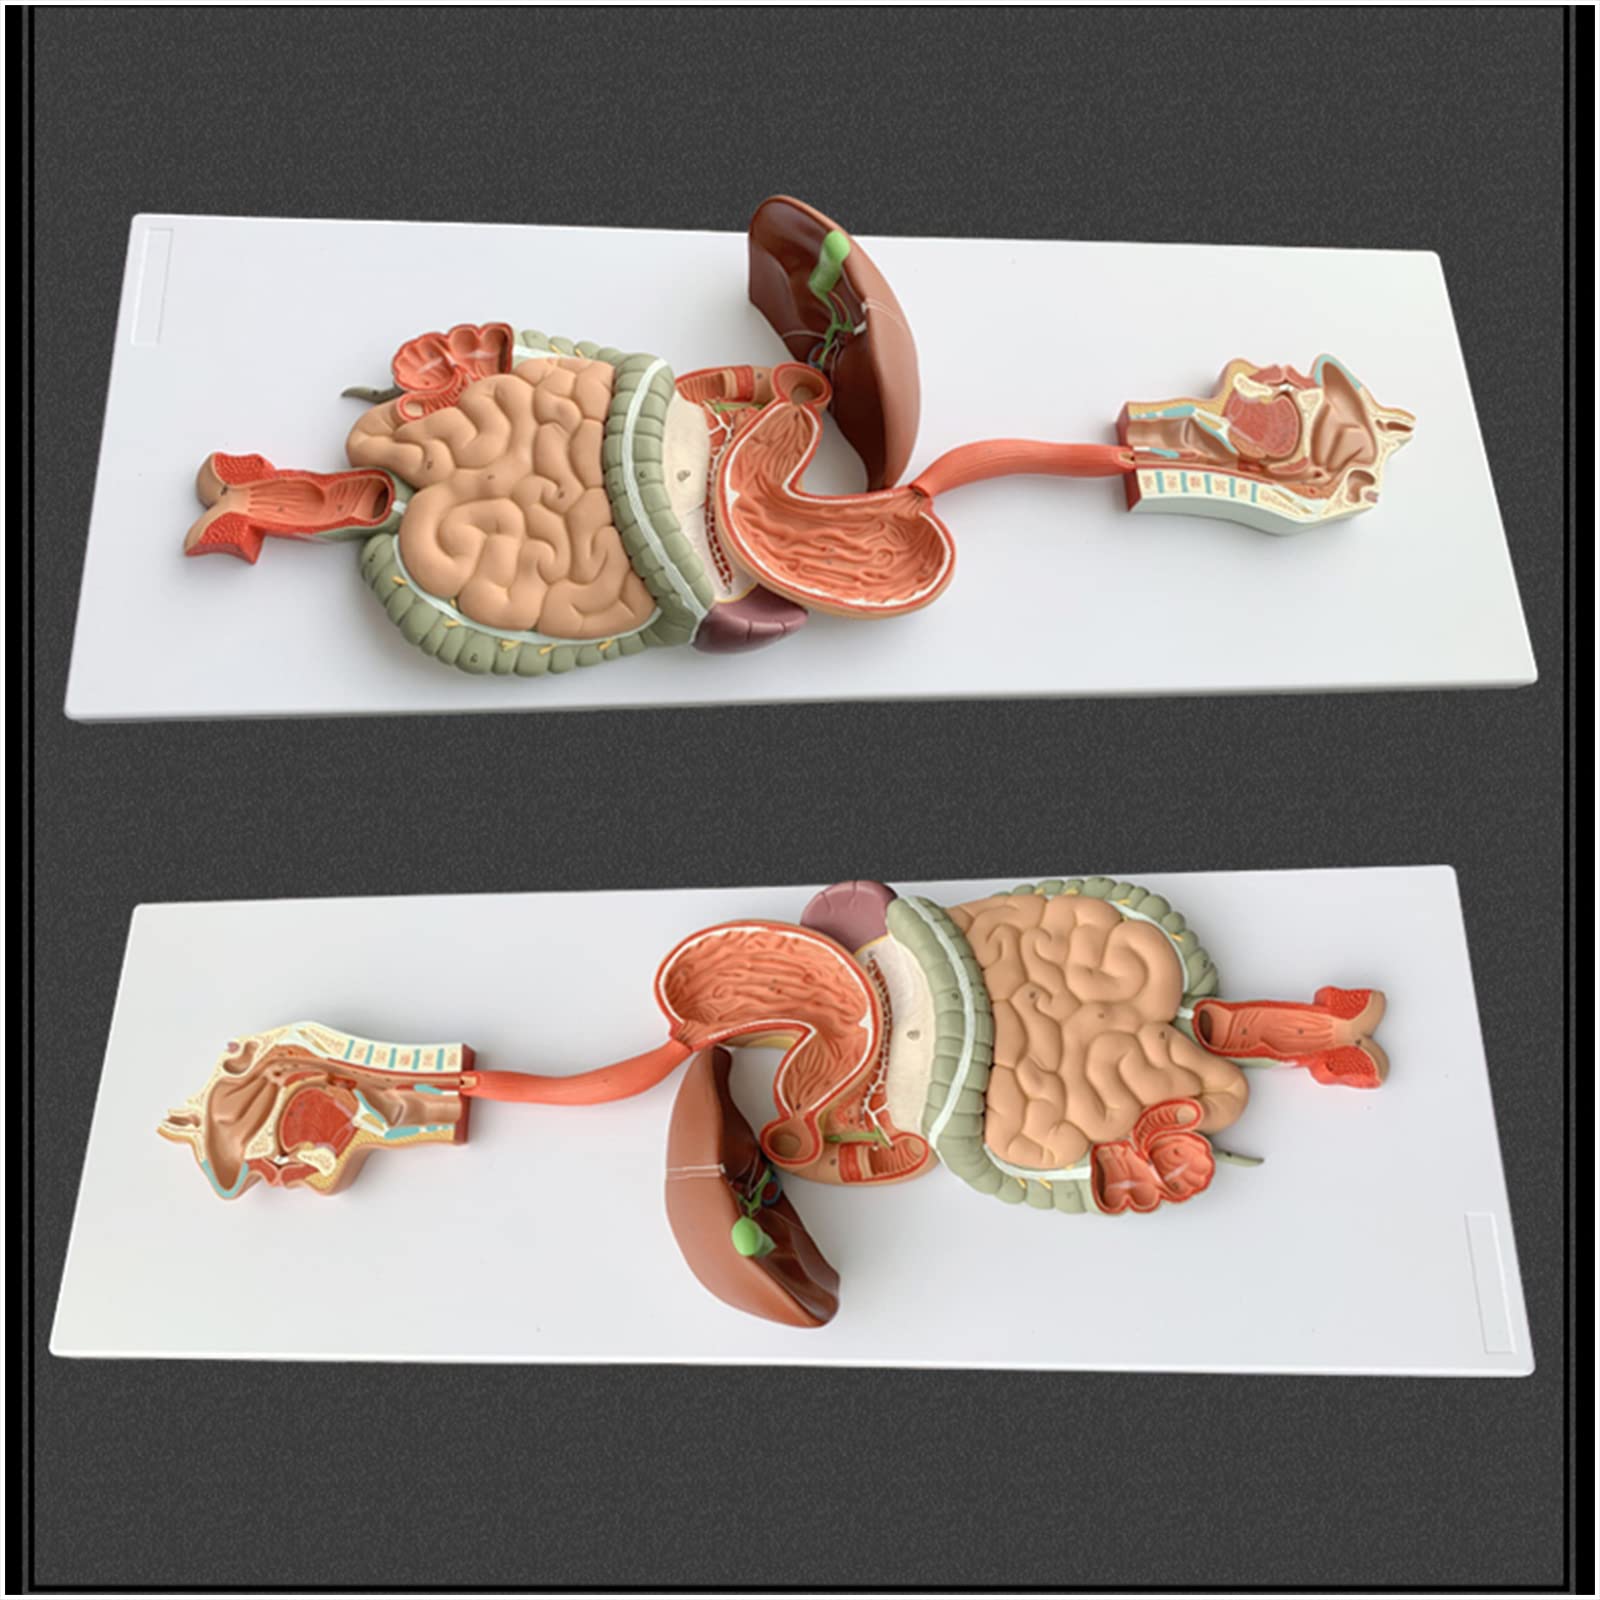

- ENHANCE PATIENT EDUCATION - Empower your clients with clear visual aids for better understanding!

- PERFECT FOR ANATOMY ENTHUSIASTS - Elevate your understanding of the human body with this detailed model!

- IDEAL FOR EDUCATORS AND STUDENTS - Transform your classroom into a hub of anatomical discovery!

The Human Digestive System Model is a life-size, three-dimensional representation of the human digestive tract, designed for educational purposes. It features disassemblable parts for interactive learning and is made from durable, anti-corrosive PVC material, making it an essential tool for anatomy students, educators, and healthcare professionals.